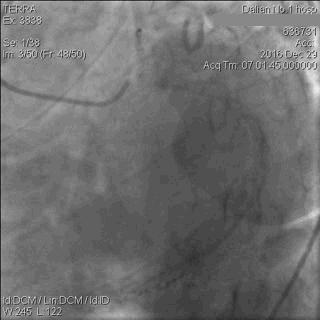

CAG显示,患者LAD中段以下闭塞;LCx近段轻中度狭窄,远段重度狭窄,钝缘支(OM)开口闭塞;RCA细小,且伴弥漫性轻中度狭窄,如图5。

图5 急诊CAG图像